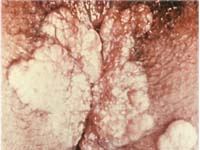

������������� ��������� ���������� ���������� ������ ������ ��������� ��������. ��������� ������� ��������� ��� ������ �������� � ������� ��� ����� ��� ������ ����. ��������� ���������� � ������ �� 3 ������ �� 9 ������� ����� ���������.